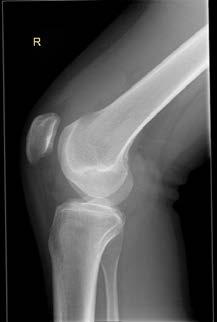

sá sem er mikilvægastur fyrir stöðugleika hnéskeljarinnar. Hnéskelin snertir trissuna fyrst við 20 til 30° beygju um hnéð og við frekari beygju helst hnéskelin stöðug vegna lögunar trissunnar (mynd 1)

Mynd 1

Hliðlægt

Miðlægt